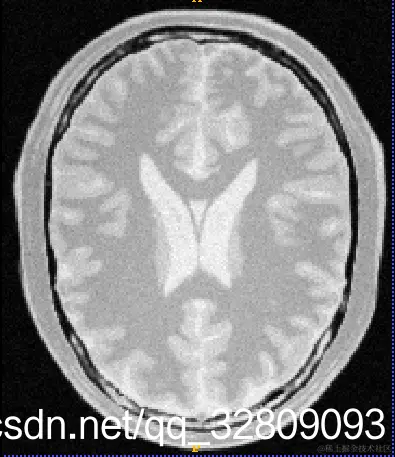

输入三维图像(BrainProtonDensity3Slices.mha):

切片1                                     切片2                                        切片3